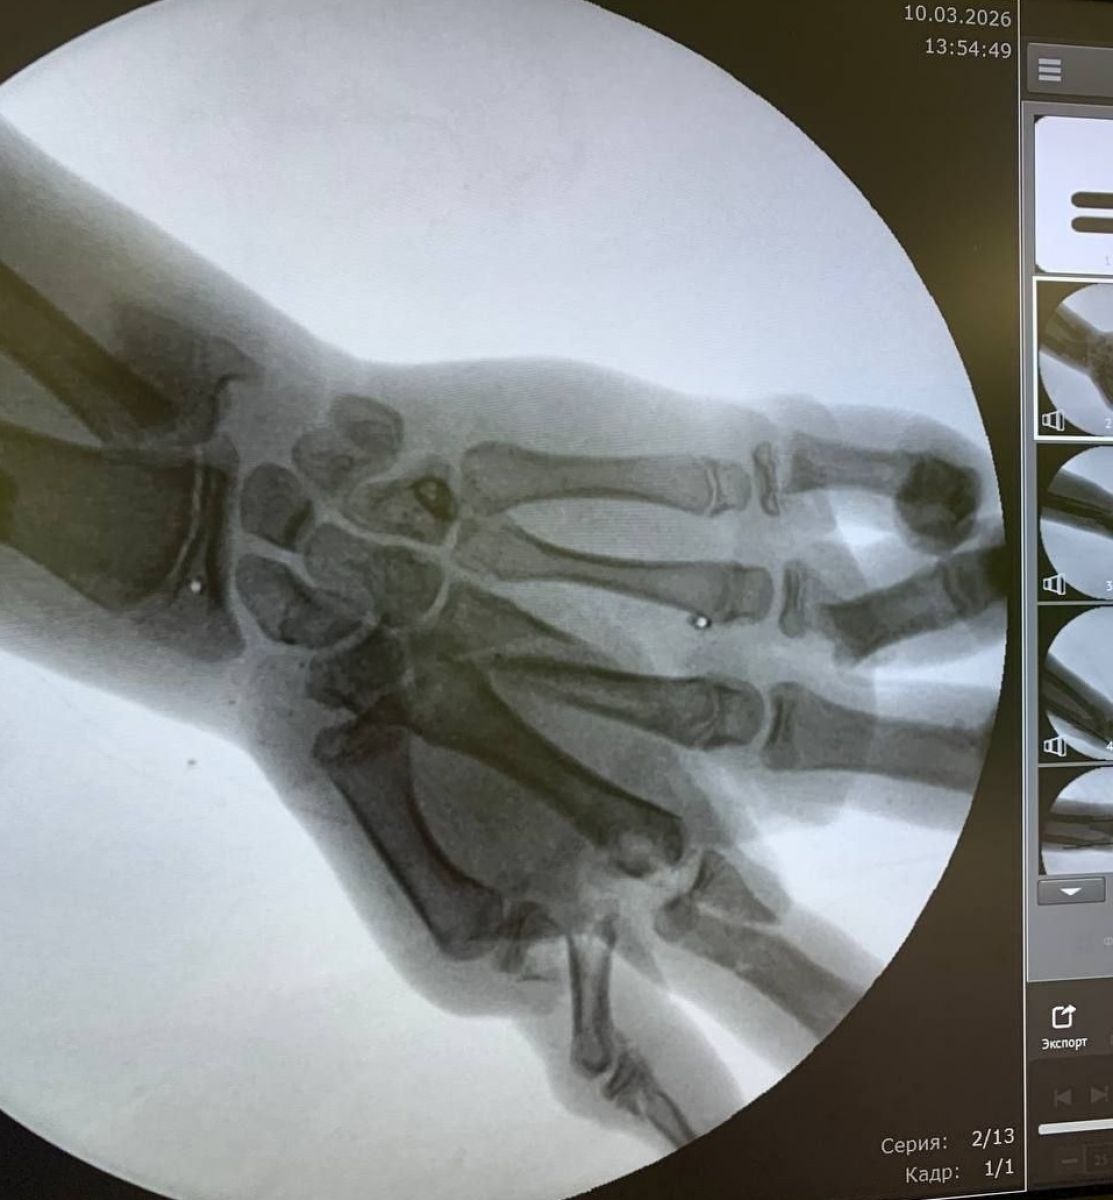

С тяжелыми травмами мальчика доставили в больницу в шоковом состоянии. У него были перелом предплечья со смещением, раны на ноге и лбу, но самое опасное — множественные переломы и сильное кровотечение в левой кисти. Врачи опасались, что конечность могут не спасти.

Специалисты немедленно провели операцию, которая длилась полтора часа. Хирургам удалось остановить кровотечение, очистить раны от загрязнений и собрать костные обломки кисти. Главной задачей было восстановить кровоток в поврежденной руке.

Из-за особенностей взрывных травм сразу невозможно точно определить, какие ткани погибли, а какие можно спасти. Через несколько дней врачи провели вторую операцию, во время которой устранили дефекты тканей и костей с помощью пластики.